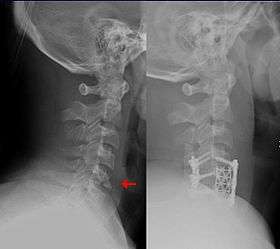

This fracture of the lower cervical vertebrae, known as a "teardrop fracture", is one of the conditions treated by orthopedic surgeons and neurosurgeons.